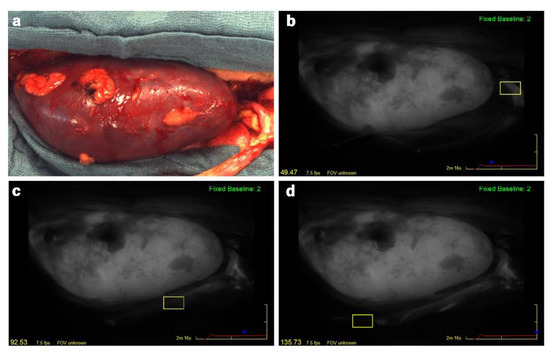

2.2. Surgical Procedure and ICG Fluorescence Angiography

2.3. Analysis of Fluorescence Angiography Video Sequences and the Ureteral Perfusion